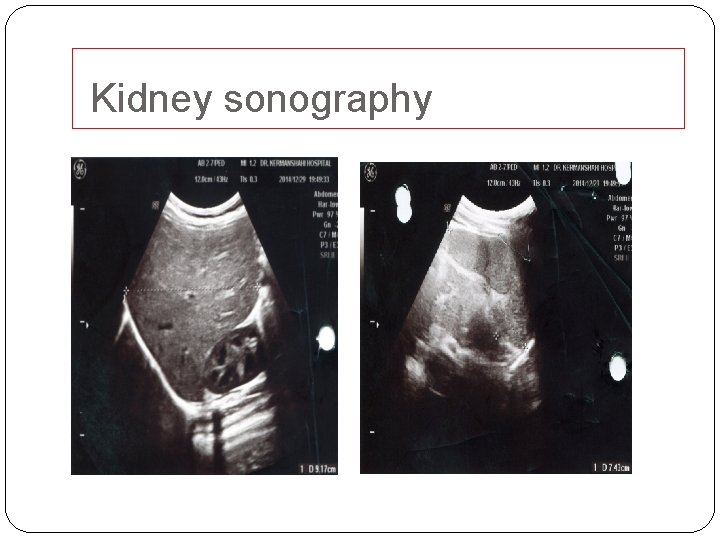

Kidney sonography

�Our patient had no history of trauma or manipulation of genital area. Negative urine culture, normal coagulation and electrophoresis test ruled out UTI, coagulopathy and sickle cell disease/trait, respectively. �According to normal kidney sonography, renal stone and malignancies are not considered. �No evidences of nephritis were observed included normal BUN, normal creatinine, no proteinuria, and being normotensive. �There was no history of drug-induced hemorrhagic cystitis.